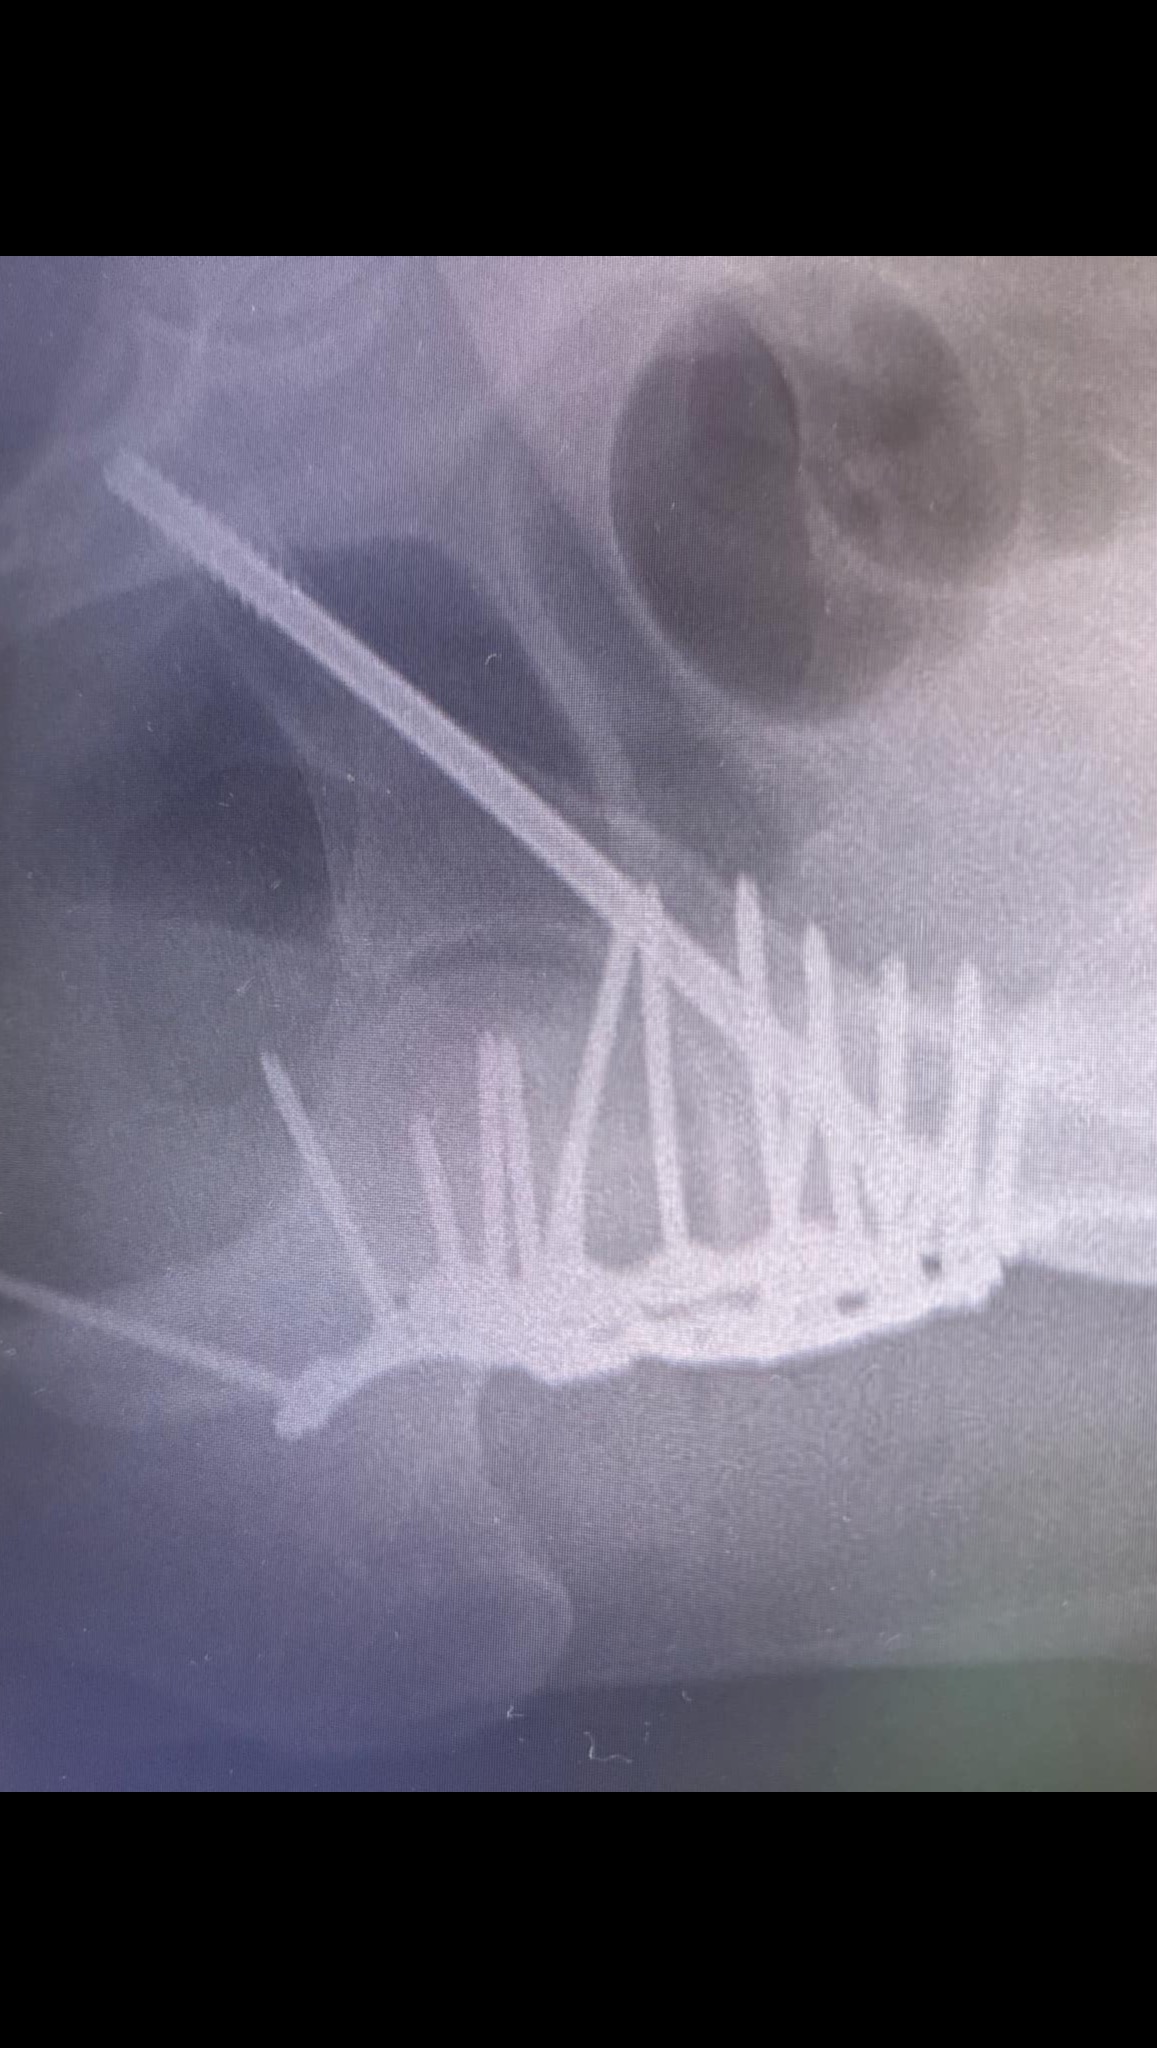

Tyler broke his Hip, Elbow, (bone is sticking out ) and he Broke his vertebrae T7-T11

he has had his surgeries on his spine, hip and elbow.